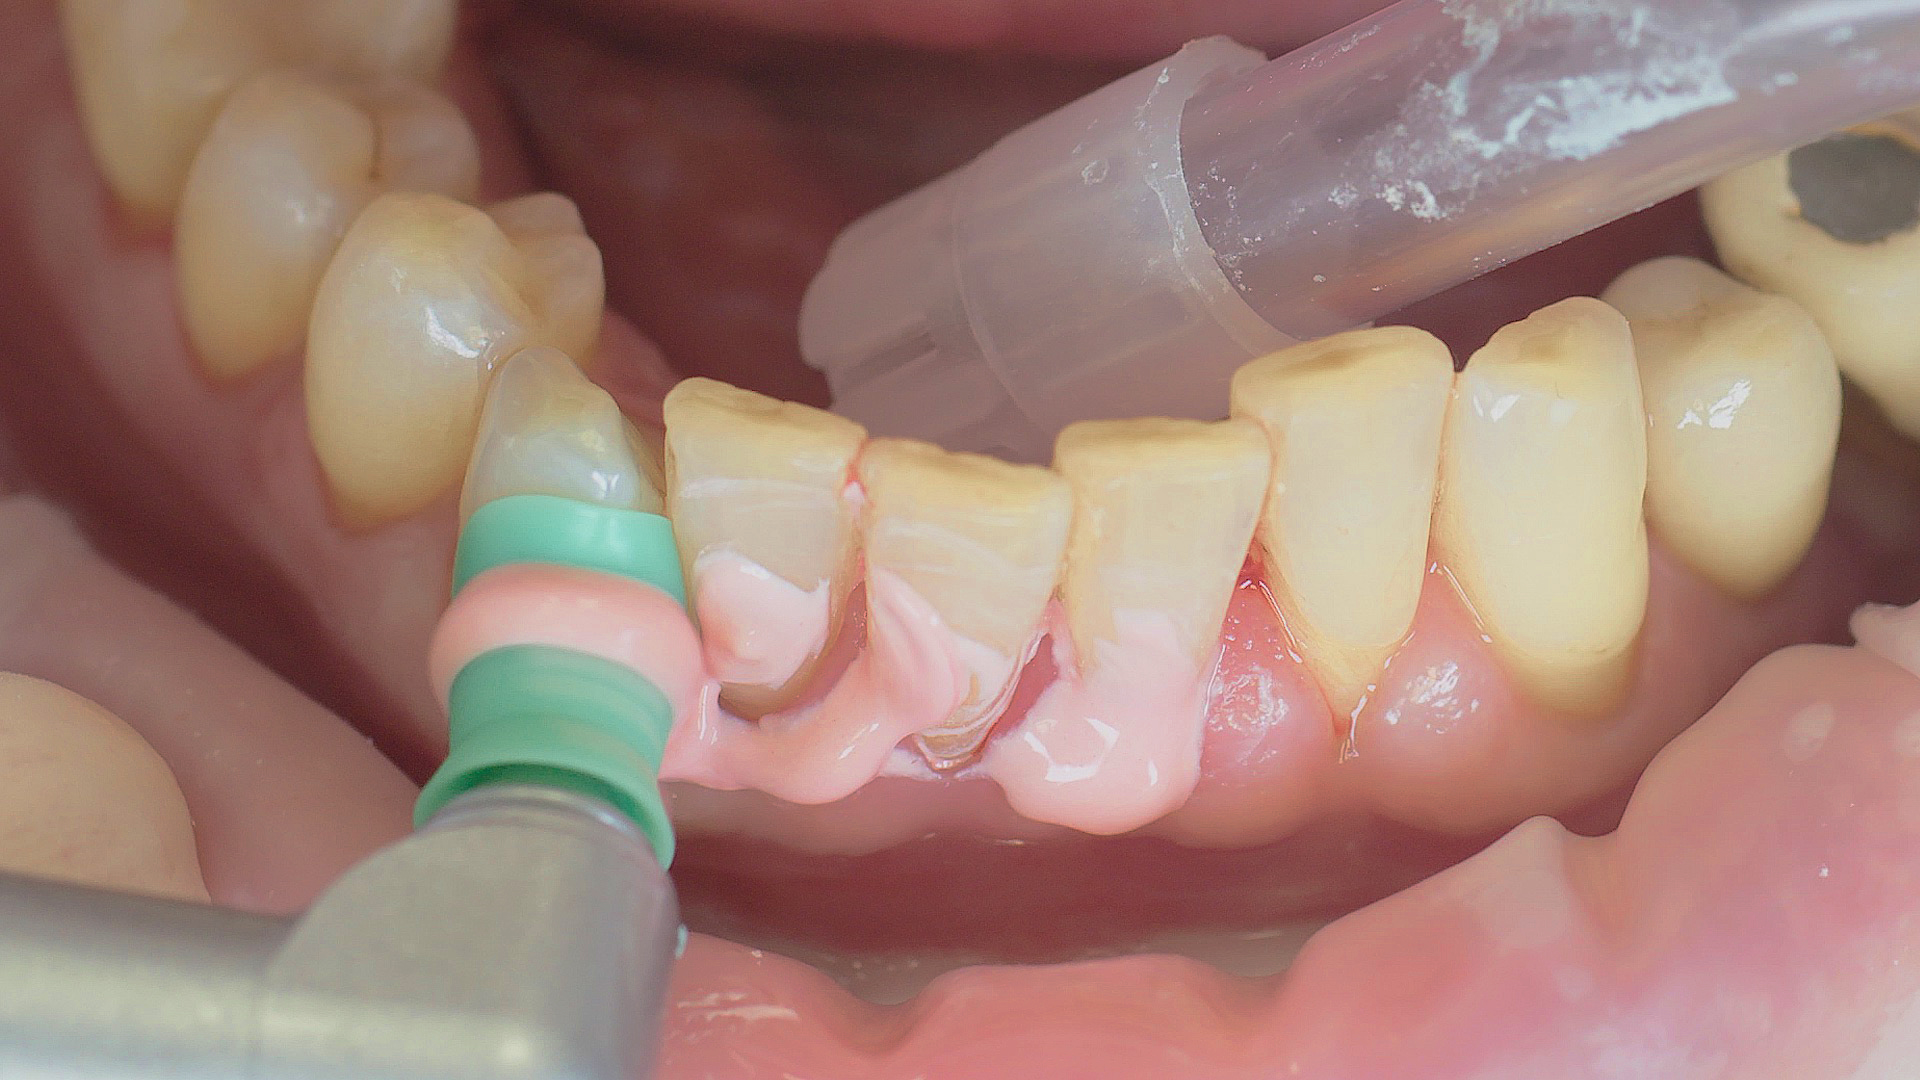

Dans les soins de suivi parodontal post-implantation, les concrétions molles (biofilm) et dures doivent être éliminées régulièrement par des techniques de nettoyage mécanique professionnelles. [16, 17] Dans les zones subgingivales et supragingivales, on utilise généralement pour cela des dispositifs à ultrasons (Fig. 4) en combinaison avec des instruments manuels si nécessaire.

L’aéropolissage subgingival peut également être utilisé, associé à des accessoires parodontaux ainsi qu’à des poudres.[18]